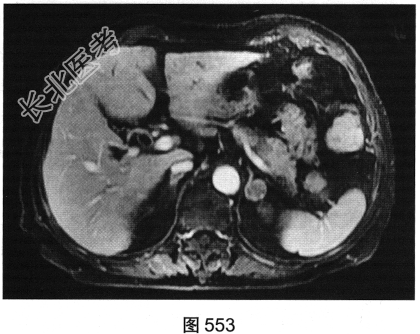

- 多项选择题3.[提示]MRI平扫+增强(图550~图555):T1WI正相位, 左侧肾上腺外侧肢可见类圆形T1WI稍高信号结节。T1WI反相位,结节信号明显减低。T2WI脂肪抑制, 结节呈均匀低信号。动态增强,动脉期结节轻度均匀强化, 静脉期结节呈相对低信号,延迟期结节呈相对低信号。可考虑的鉴别诊断为( )